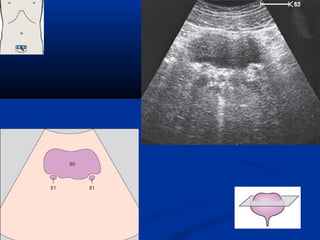

bladderbladder

258